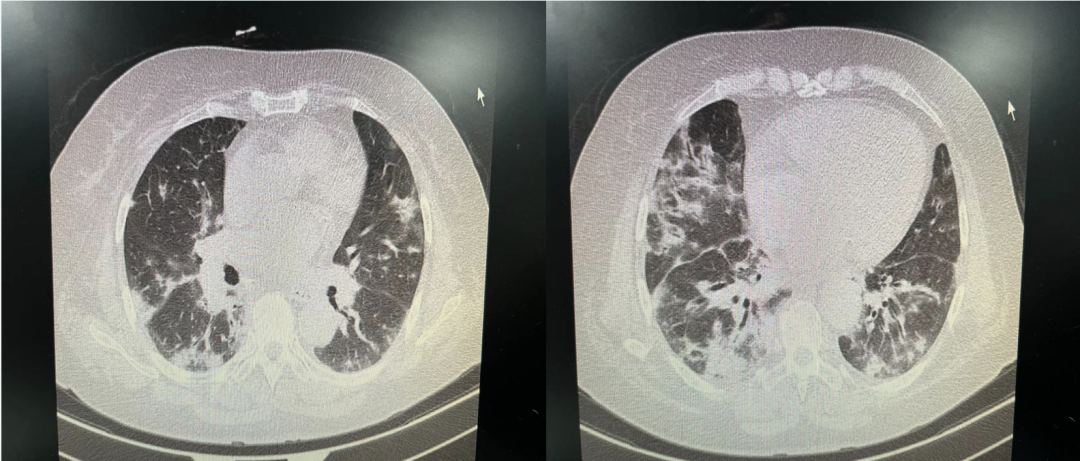

• 胸部CT:双肺支气管血管束增粗、部分小叶间隔增厚伴浅淡磨玻璃影,间质性肺水肿不除外

• 左肺舌段及右肺中叶内侧段小叶性肺不张。

• 心脏增大,心包积液;心腔密度减低,符合贫血改变。

• 纵隔、双侧锁骨区及腋窝肿大淋巴结

• 双侧胸腔积液,伴邻近肺组织膨胀不全。

• 胸壁皮下软组织水肿。

image.png